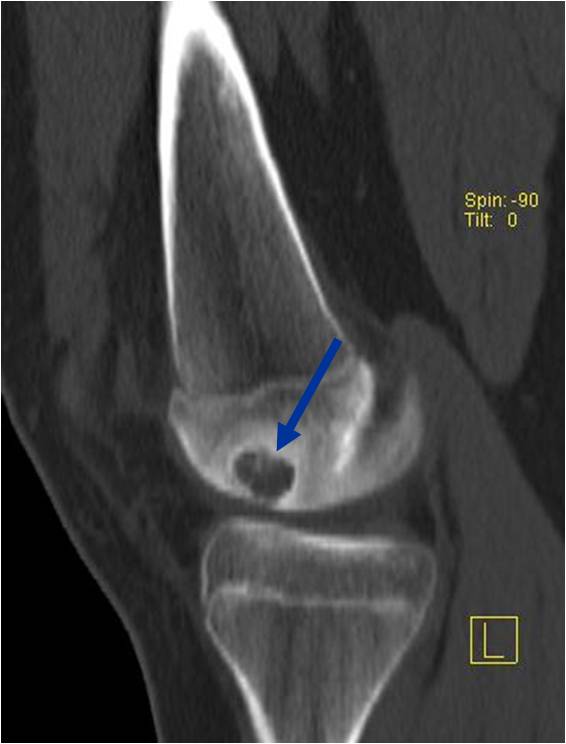

CT appearance:

- Most useful for detecting subtle mineralization not apparent on X-rays

- Useful for identifying intact periosteum around any expansile soft tissue component

- surrounding thin reactive shell of bone/mineralization (Egg Shell Rim of Calcification)

- helps place the tumor in a benign category

- helps evaluate:

- bony quality

- extent of bone and cortical destruction

- whether the subchondral plate of bone adjacent to the articular cartilage has been destroyed or is intact